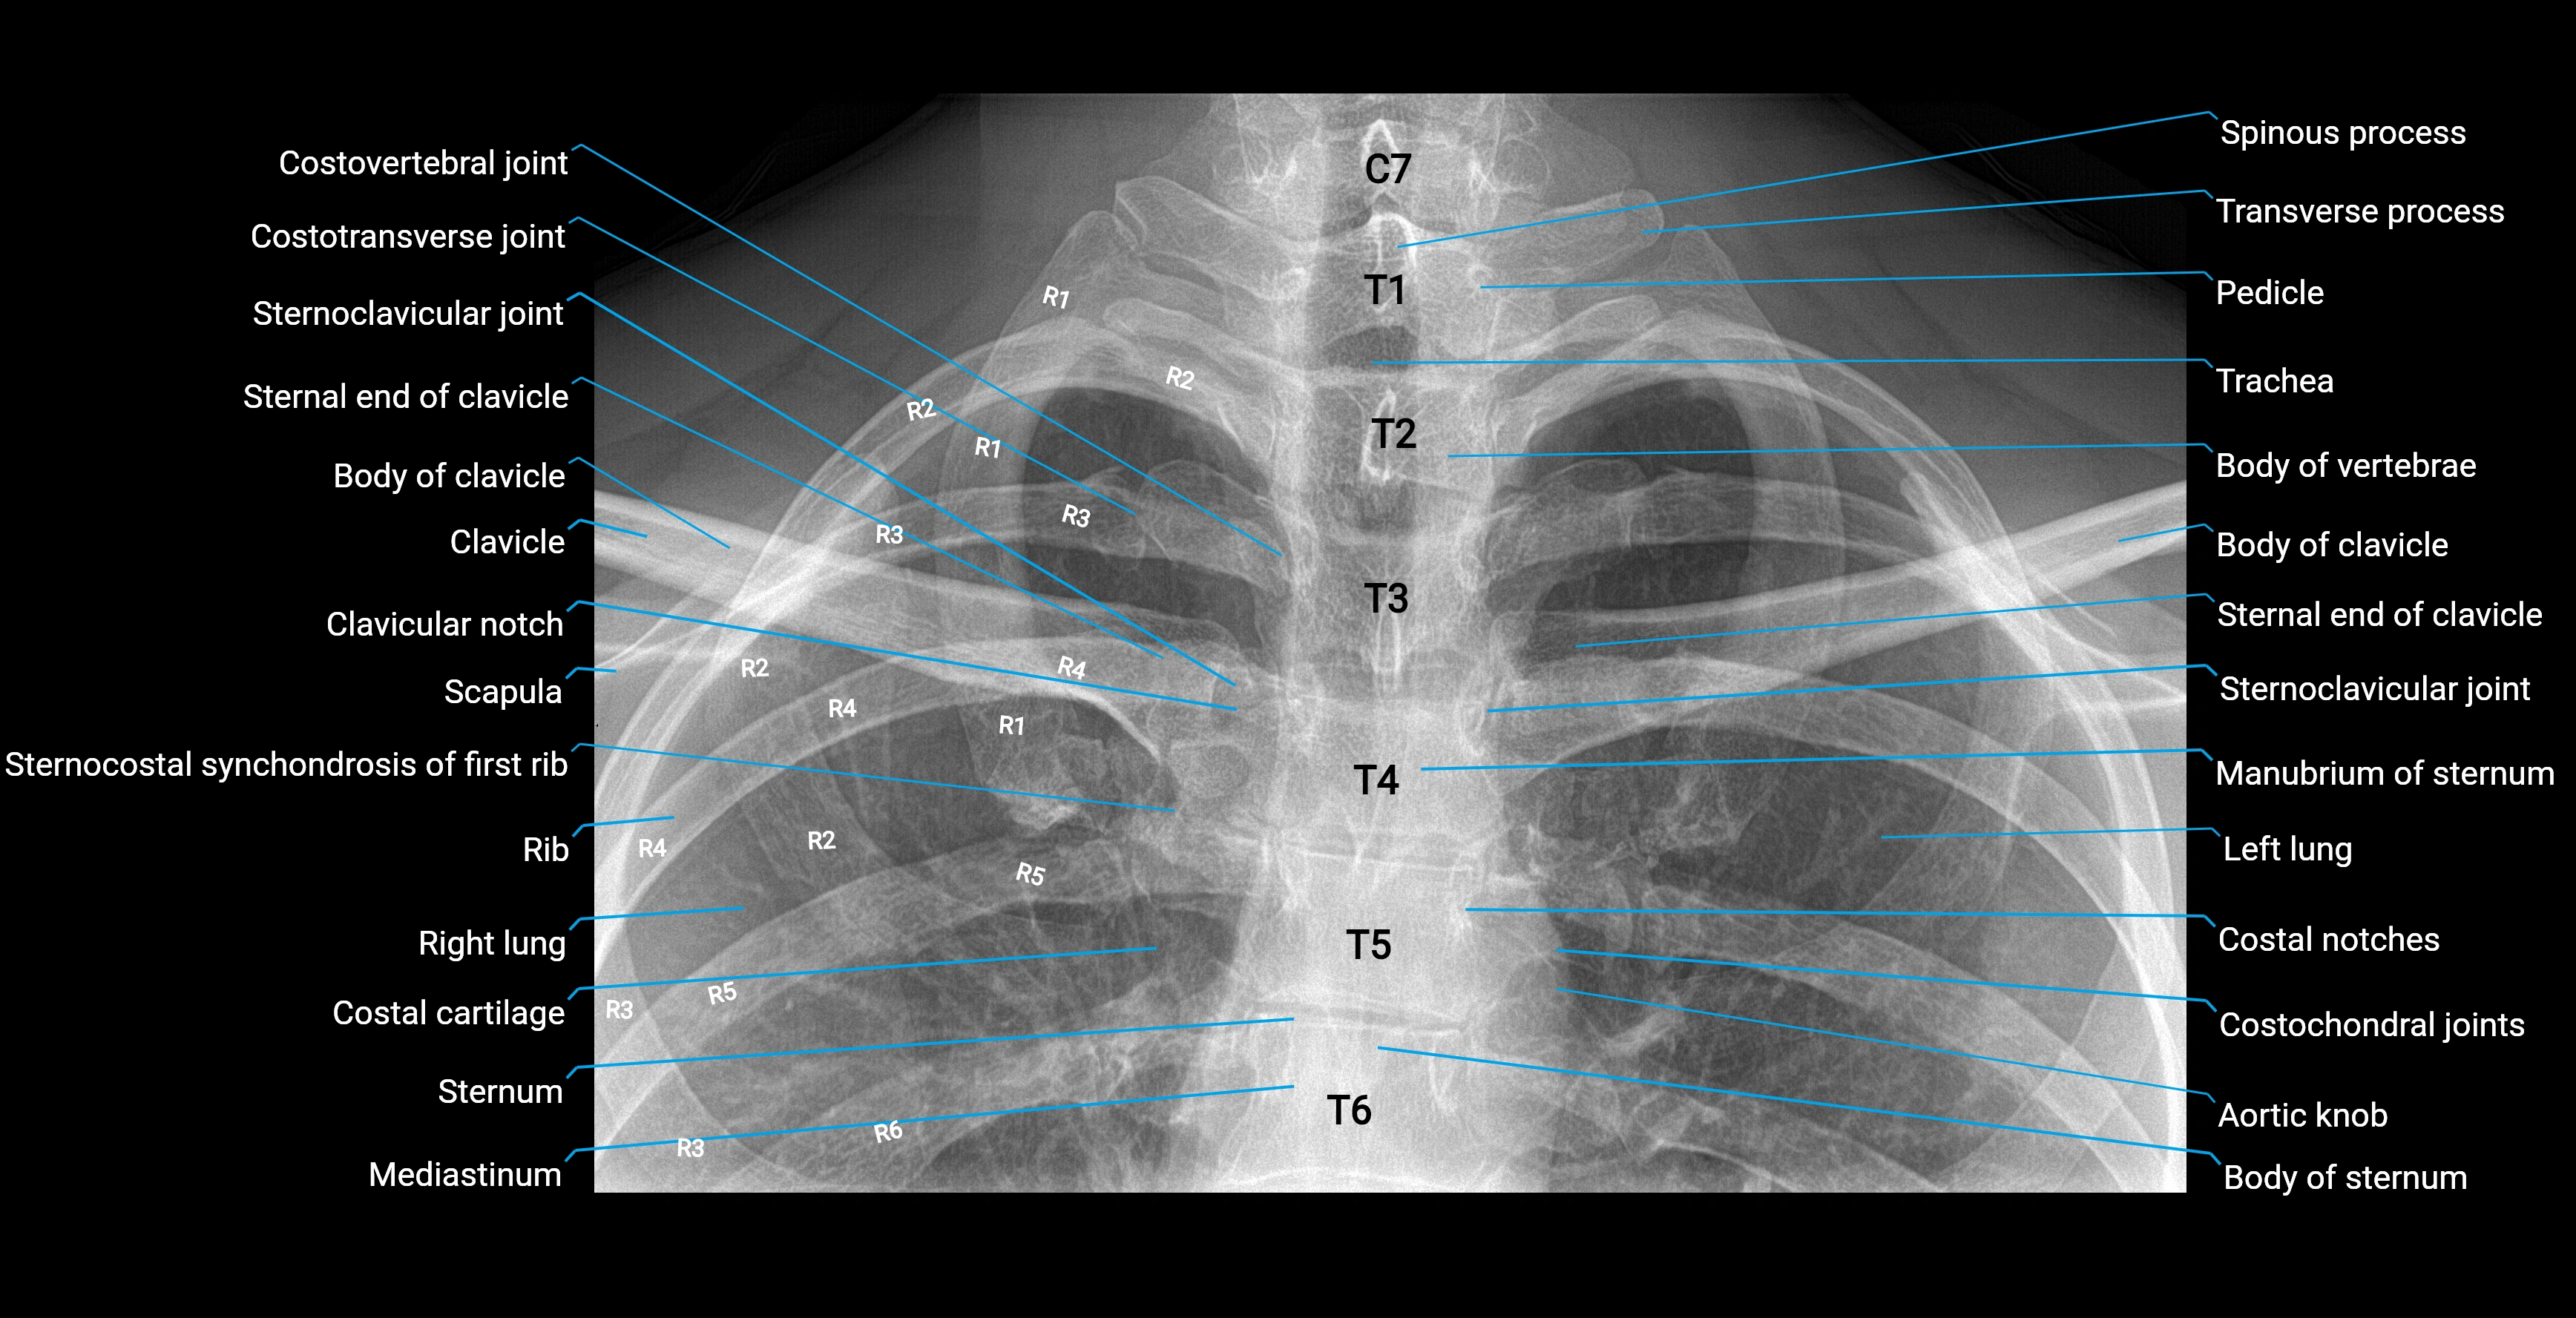

Chest radiograph (PA view):

• Aortic knob: Smooth, rounded convexity along the left upper mediastinal border

• Margins: Well-defined and continuous

• Position: Above the left hilum

• Size and contour: Influenced by patient age, body habitus, and aortic orientation